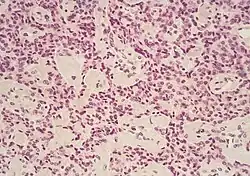

Guz gastrynowy (łac. gastrinoma, ang. gastrinoma) – guz neuroendokrynny, drugi co do częstości występowania typ wyspiaka trzustki po insulinoma[1]. Zapadalność wynosi 1:1 000 000/rok[2]. Lokalizuje się głównie w głowie trzustki i dwunastnicy. Wywodzi się z komórki G. Zwykle nie osiąga rozmiarów powyżej 1 cm. Złośliwość ocenia się na 60% przypadków. Jest najczęstszym guzem neuroendokrynnym w zespole MEN1[3]. Guzy gastrynowe mogą wydzielać oprócz gastryny również ACTH.